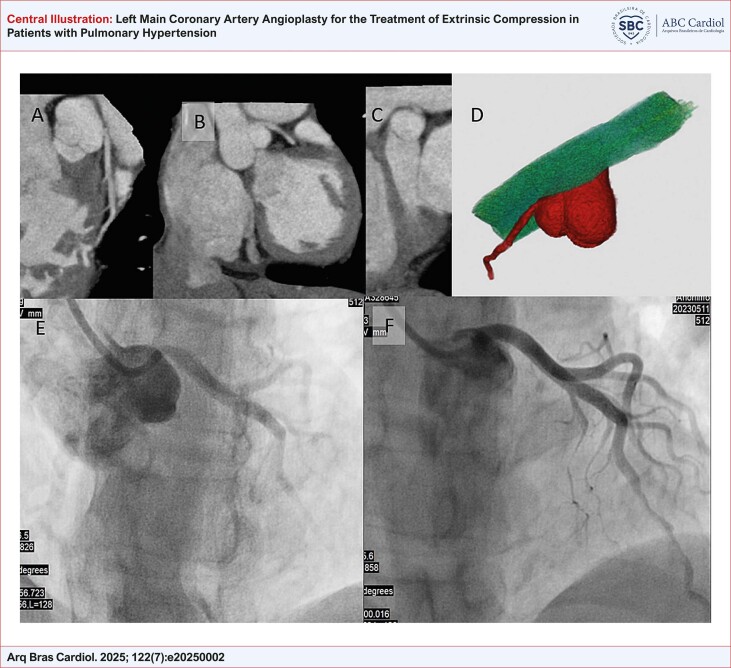

背景:肺动脉高压(PH)最常见的临床表现包括用力性呼吸困难、全身充血和晕厥。心绞痛也可能是一个相关的表现,特别是当左主干冠状动脉(LMCA)被扩张的肺动脉外部压迫时。然而,在这种临床情况下,关于冠状动脉阻塞最合适的诊断和治疗策略仍然存在重大差距。目的:评价冠状动脉成形术联合支架植入术对PH合并LMCA外源性压迫患者症状缓解的可行性及影响。方法:本描述性研究纳入了12例PH患者,这些患者在巴西巴西圣保罗大学医学院医院cora 研究所肺循环门诊接受随访。所有患者均行冠状动脉成形术合并支架植入治疗LMCA外源性压迫。结果:共分析12例患者,平均年龄47.9岁,以1组PH为主,接受特异性治疗。所有的手术都取得了极好的立竿见影的效果,30天后心绞痛得到缓解。在平均33个月的随访期间,无手术相关并发症报告,心绞痛症状得到控制。4名患者死于进行性心力衰竭。结论:研究结果支持冠脉血管成形术作为一种缓解LMCA压迫合并ph患者心绞痛症状的策略的可行性。需要进一步的研究来评估这种干预对硬临床结果的影响,以及在无症状患者中的筛查作用。

Background: The most common clinical presentation of pulmonary hypertension (PH) includes exertional dyspnea, signs of systemic congestion, and syncope. Angina pectoris can also be a relevant manifestation, especially in cases where the left main coronary artery (LMCA) is externally compressed by a dilated pulmonary artery. However, significant gaps remain regarding the most appropriate diagnostic and therapeutic strategies for coronary obstruction in this clinical scenario.

Objectives: To assess the feasibility and impact of coronary angioplasty with stent implantation on symptom relief in patients with PH and extrinsic compression of LMCA.

Methods: This descriptive study included 12 patients with PH who were followed at the Pulmonary Circulation Outpatient Clinic of the Instituto do Coração, Hospital das Clínicas da Faculdade de Medicina da Universidade de São Paulo. All patients underwent coronary angioplasty with stent implantation to treat extrinsic compression of LMCA.

Results: A total of 12 patients were analyzed, with a mean age of 47.9 years, predominantly with group 1 PH and under specific therapy. All procedures achieved excellent immediate results, with angina relief observed at 30 days. During a mean follow-up of 33 months, no procedure-related complications were reported, and angina symptoms remained controlled. Four patients died due to progressive heart failure.

Conclusion: The findings support the feasibility of coronary angioplasty as a strategy for symptomatic relief of angina in patients with LMCA compression associated with PH. Further studies are needed to evaluate the impact of this intervention on hard clinical outcomes, as well as the role of screening in asymptomatic patients.